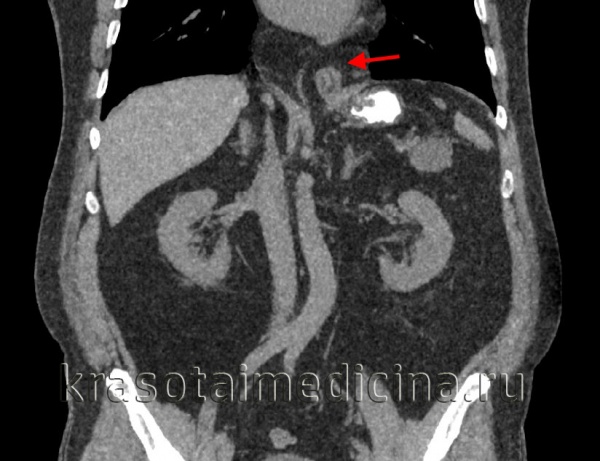

КТ ОБП (3D-реконструкция) пищевода и желудка. Аксиальная грыжа пищеводного отверстия диафрагмы, пищеводно-желудочный переход и кардия (красная стрелка) в грудной полости. Желудок (синяя стрелка), пищевод (зеленая стрелка).